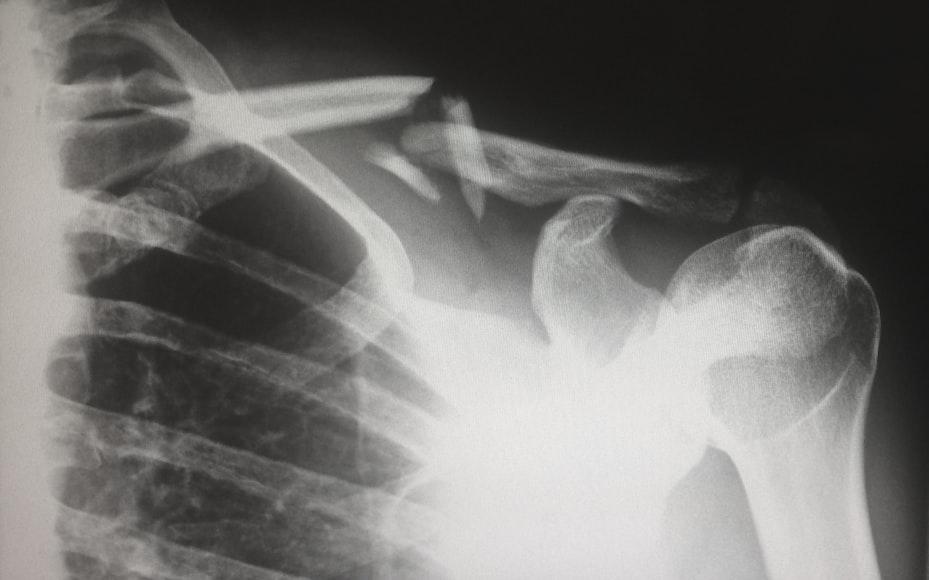

Photo by Harlie Raethel